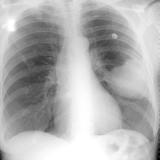

Lung Cancer

Nodules & Masses

Album: Nodules & Masses